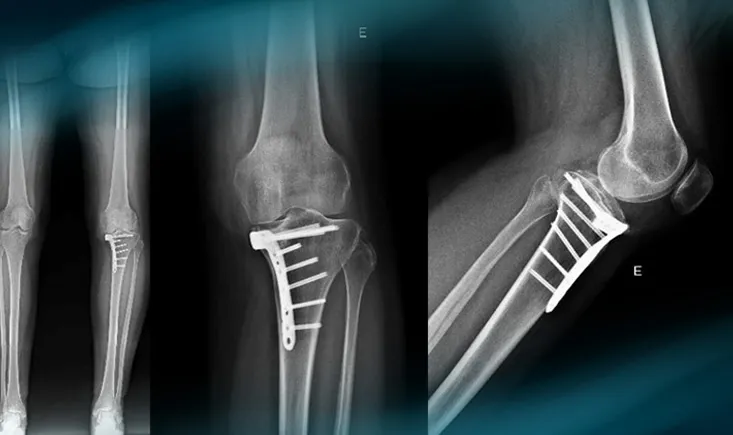

The goals of this clinical case are to discuss the different therapeutic options in case of vicious callus of…